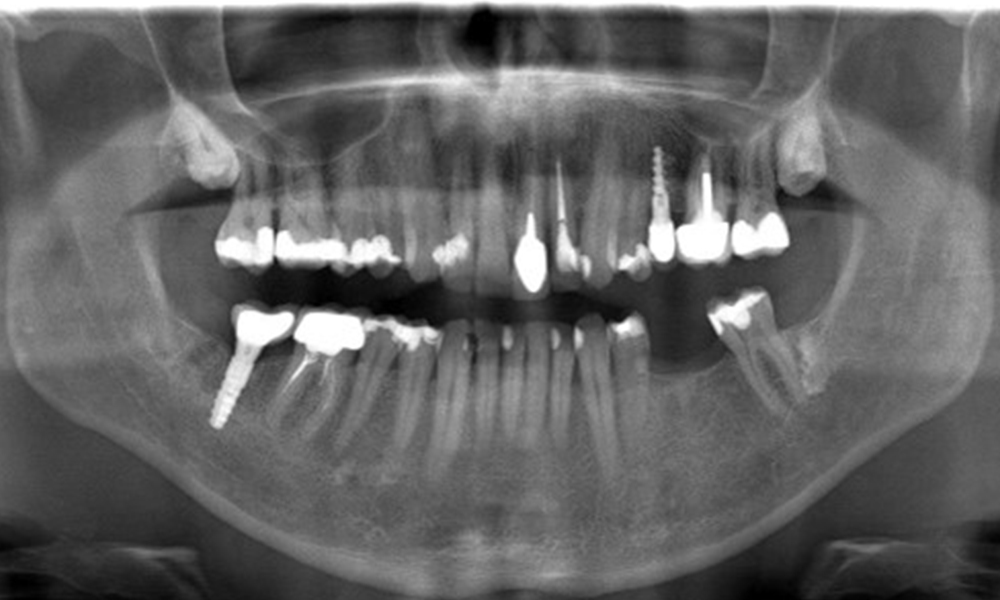

OPG: 29.02.2024

Röntgenaufnahme zeigt Knochenabbau

Die Röntgenaufnahme zeigt den Knochenabbau.

Der Patient hat einige zahnärztliche Restaurationen und zwei Implantate (2. und 4. Quadrant). Anhand der aktuellen Befunde lässt sich eine Gingivitis bei stabilem parodontalen Zustand am reduzierten Parodont (Stadium III, Grad A) feststellen.

Versorgungen: zahnärztliche Restaurationen (NEM keramisch verblendet), zwei Implantate (2., 4. Quadrant)